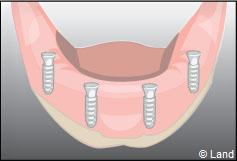

Les implants peuvent aussi servir à stabiliser un appareil amovible au maxillaire supérieur comme au maxillaire inférieur. Dans ce cas, les implants retiennent la prothèse amovible par des systèmes d’attachement.

Deux techniques sont possibles. Elles font appel à la barre de rétention ou aux boutons-pressions.

Exemple d’une réhabilitation complète implantaire